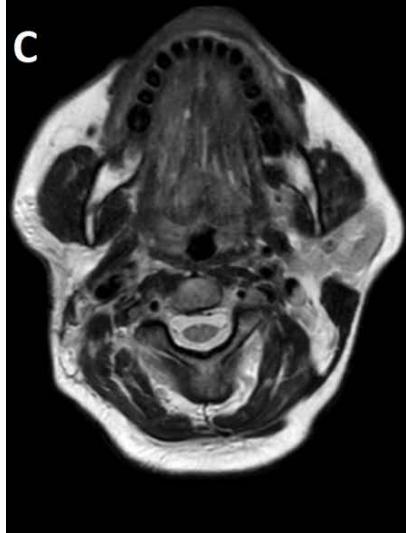

Figure/Patient 2

A case of right mandibular lymphangioma in a 10 year-old boy, hypoechoic with some septations and no blood vessels (A) and hyper-intense on T2 axial (B) and coronal (C) MR scans.